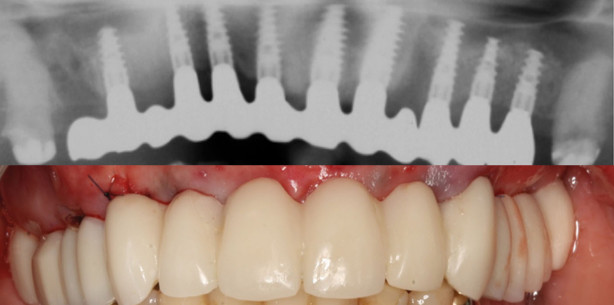

Über die dreidimensionale Bildgebung mit einem CT bzw. DVT können computergestützt Planungs- und Versorgungskonzepte für die Durchführung von elektiven implantologischen Eingriffen erstellt werden. Verschiedene computerassistierte Softwaresysteme stehen dabei derzeit für nahezu alle führenden Implantathersteller zur Verfügung, mit zum Teil jedoch sehr unterschiedlichem Workflow. Das navigierte Vorgehen ermöglicht es, die Implantatpositionen und Längen entsprechend des vorhandenen Knochenangebotes, dennoch orientiert an der prothetischen Vorgabe, zu planen. Ziel ist es, aufwendige Knochenaugmentationen zu umgehen, die Anzahl der Eingriffe zu reduzieren und deutlich minimalinvasiver zu gestalten, wodurch sowohl das OP-Trauma als auch allgemeine Komplikationen deutlich minimiert werden. Eine Möglichkeit der Vermeidung von vertikalen Augmentationen besteht in der Insertion kurzer Implantate, wie in Abbildung 5 dargestellt (Brånemark 3,75 x 8,5 mm). Die Implantate wurden mit der Nobel Guide Software geplant (Abb. 6 und 7) und flapless bei einem Patienten unter ASS 100 Medikation durch die Operationsschablone inseriert. Abbildung 8 zeigt das Kontrollbild vier Jahre postoperativ. Geringes Knochenangebot, wie Abbildung 9 zeigt, kann optimal genutzt werden. Abbildungen 10 und 11 zeigen Ausschnitte aus der Planung mit maximaler Ausnutzung des geringen Knochenangebotes. Eine enge Zusammenarbeit mit dem Zahntechniker ist bei der Planung wie auch bei der Umsetzung der navigierten Arbeitsabläufe Voraussetzung für den Behandlungserfolg. Abbildung 12 zeigt die geteilte Stegkonstruktion und Abbildung 13 das fünf Jahre postoperative Kontrollbild.

Des Weiteren ist es möglich, durch die exakte präoperative Längenbestimmung des Restknochenangebotes im Seitenzahnbereich des Oberkiefers im DVT und die exakte Führung der Operationsschablonen in ausgewählten Fällen einen internen Sinuslift an stelle eines externen durchzuführen. Spezielle Osteotome mit individuell montierten Stopps verhindern ein zu weites Eindringen in den Sinusbereich (Abb. 14). Zudem kann in ausgewählten Fällen die Implantatversorgung im Sinne eines sogenannten „Backward Plannings“ ausgehend von einem angestrebten, optimalen Therapieziel bzw. einer bereits im Vorfeld konstruierten Prothetik geplant werden. Hierfür wird zunächst im Rahmen der präoperativen Planung der Zahnersatz nach einer ästhetischen und funktionellen Anprobe in Wachs erstellt. Durch die Verwendung einer Scanschablone (Abb. 15) oder einer Übertragung der Modell- und Wax-up-Konstruktionen über STL-Daten können anschließend die Bilddaten der Schichtaufnahme in Relation zur geplanten Prothetik gesetzt werden. Am PC können nun in der Navigationssoftware die Implantatpositionen unter Berücksichtigung der Prothetik festgelegt werden (Abb. 16 und 17). Durch die Anfertigung einer Operationsschablone (Abb. 18), die systembedingt stereolitografisch, durch Umarbeitung der Scanschablone oder durch Industriedruck hergestellt wird, können die festgelegten Implantatpositionen auf den Patienten übertragen werden. Die Genauigkeit dieses Vorgehens bietet bei einer ausreichend hohen Primärstabilität der eingebrachten Implantate die Möglichkeit einer sofortigen prothetischen Versorgung der Implantate mittels eines im Vorfeld und in Übereinstimmung mit der präoperativen Planung hergestellten provisorischen Zahnersatzes (Abb. 19). Des Weiteren erlaubt diese detaillierte präoperative Planung ein operatives Vorgehen mit einer hohen Präzision und einer großen forensischen Sicherheit. Der Eingriff und das prothetische Ergebnis (Abb. 20 und 21) werden vorhersehbarer. Die Zahl der Eingriffe konnte durch die navigierte Planung reduziert werden. Aufgrund einer ausreichend keratinisierten Gingiva (Abb. 22) wurden die Implantate im anterioren Oberkiefer und Regio 15 mit internem Sinuslift flapless inseriert, Regio 24–26 wurde ein externer Sinuslift mit sofortiger Insertion der Implantate, ohne Sofortbelastung vorgenommen. Dem häufig geäußerten Wunsch nach einer festen Versorgung kann in diesem Fall entsprochen werden (Abb. 23).